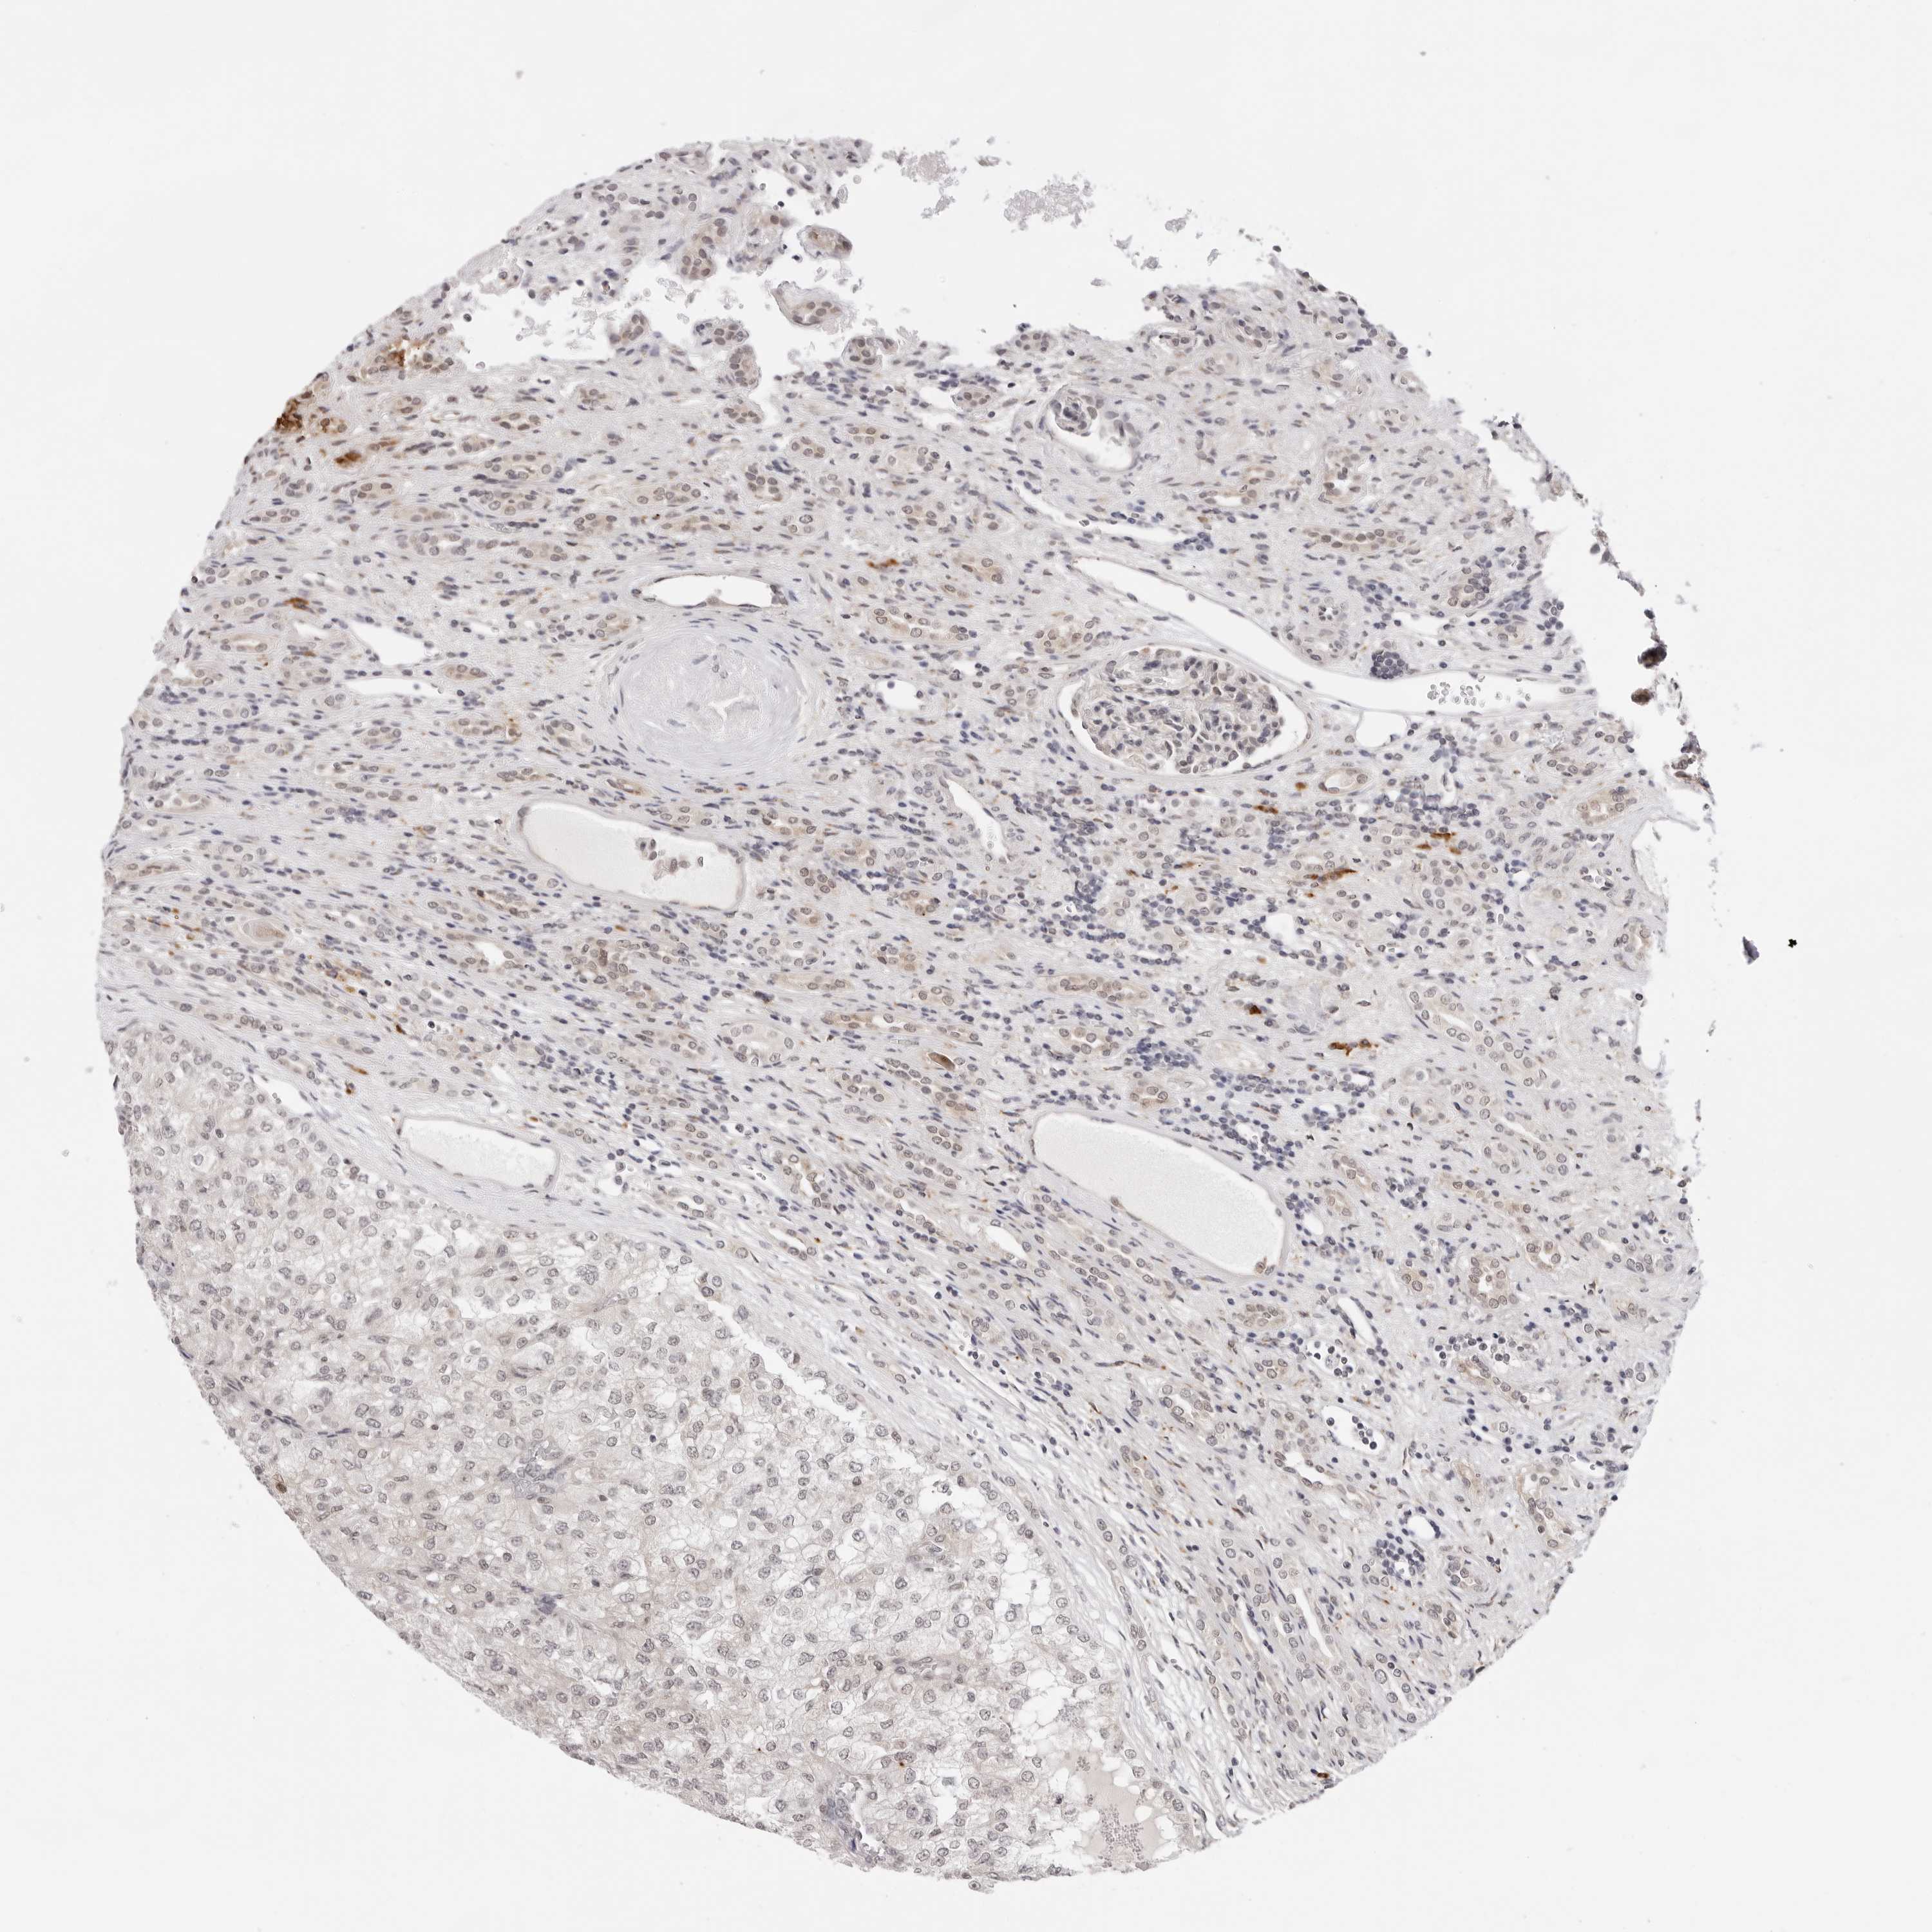

CANCER RENAL CANCER Show tissue menu

KICH TCGA KIRC TCGA KIRC VALIDATION KIRP TCGA PROTEIN RCC CPTAC PROTEIN EXPRESSION